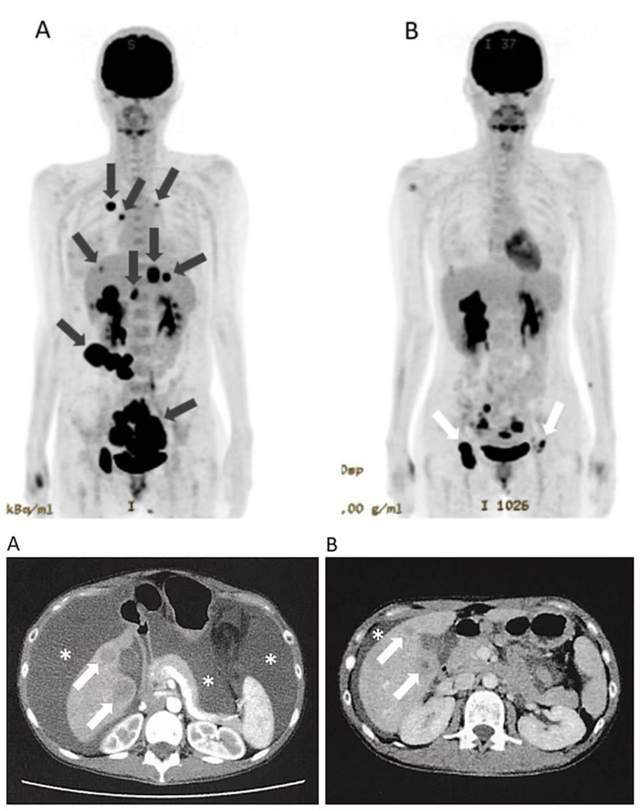

一位30多岁的女性患者,确诊时已是IV期子宫内膜癌,伴有腹膜、肝、肺、骨多处转移和大量腹水。在常规化疗效果有限的情况下,她接受了WT1-DC疫苗、高活性NK细胞联合免疫检查点抑制剂(纳武利尤单抗)的治疗。经过几个疗程,影像学复查显示,其肺转移灶和腹膜播散灶完全消失,肝转移灶显著缩小,腹水明显减少。